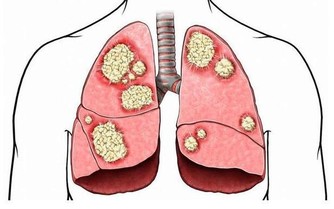

很多人都知道,養血管就是養命,血管通暢了,血液就能順利到達人體的各個器官,提供營養,一旦血管堵塞,就會出現各種不適應的症狀,甚至是危機生命。血管堵塞,不加以重視就會發展成動脈硬化,使得血管變窄、變硬,堵塞血管從而失去彈性,可以導致中風、心絞痛、下肢動脈閉塞一系列問題。